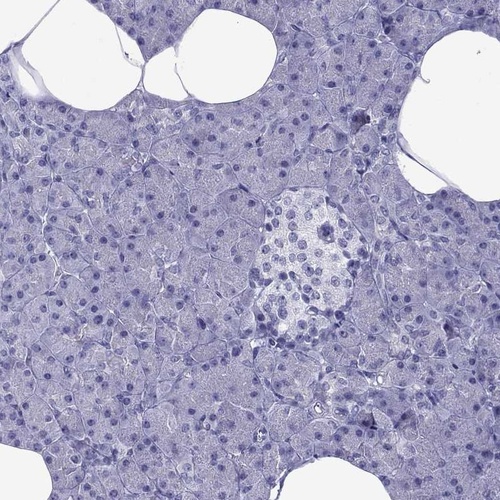

Immunohistochemistry analysis in human heart muscle and pancreas tissues using Anti-MYLK3 antibody. Corresponding MYLK3 RNA-seq data are presented for the same tissues.